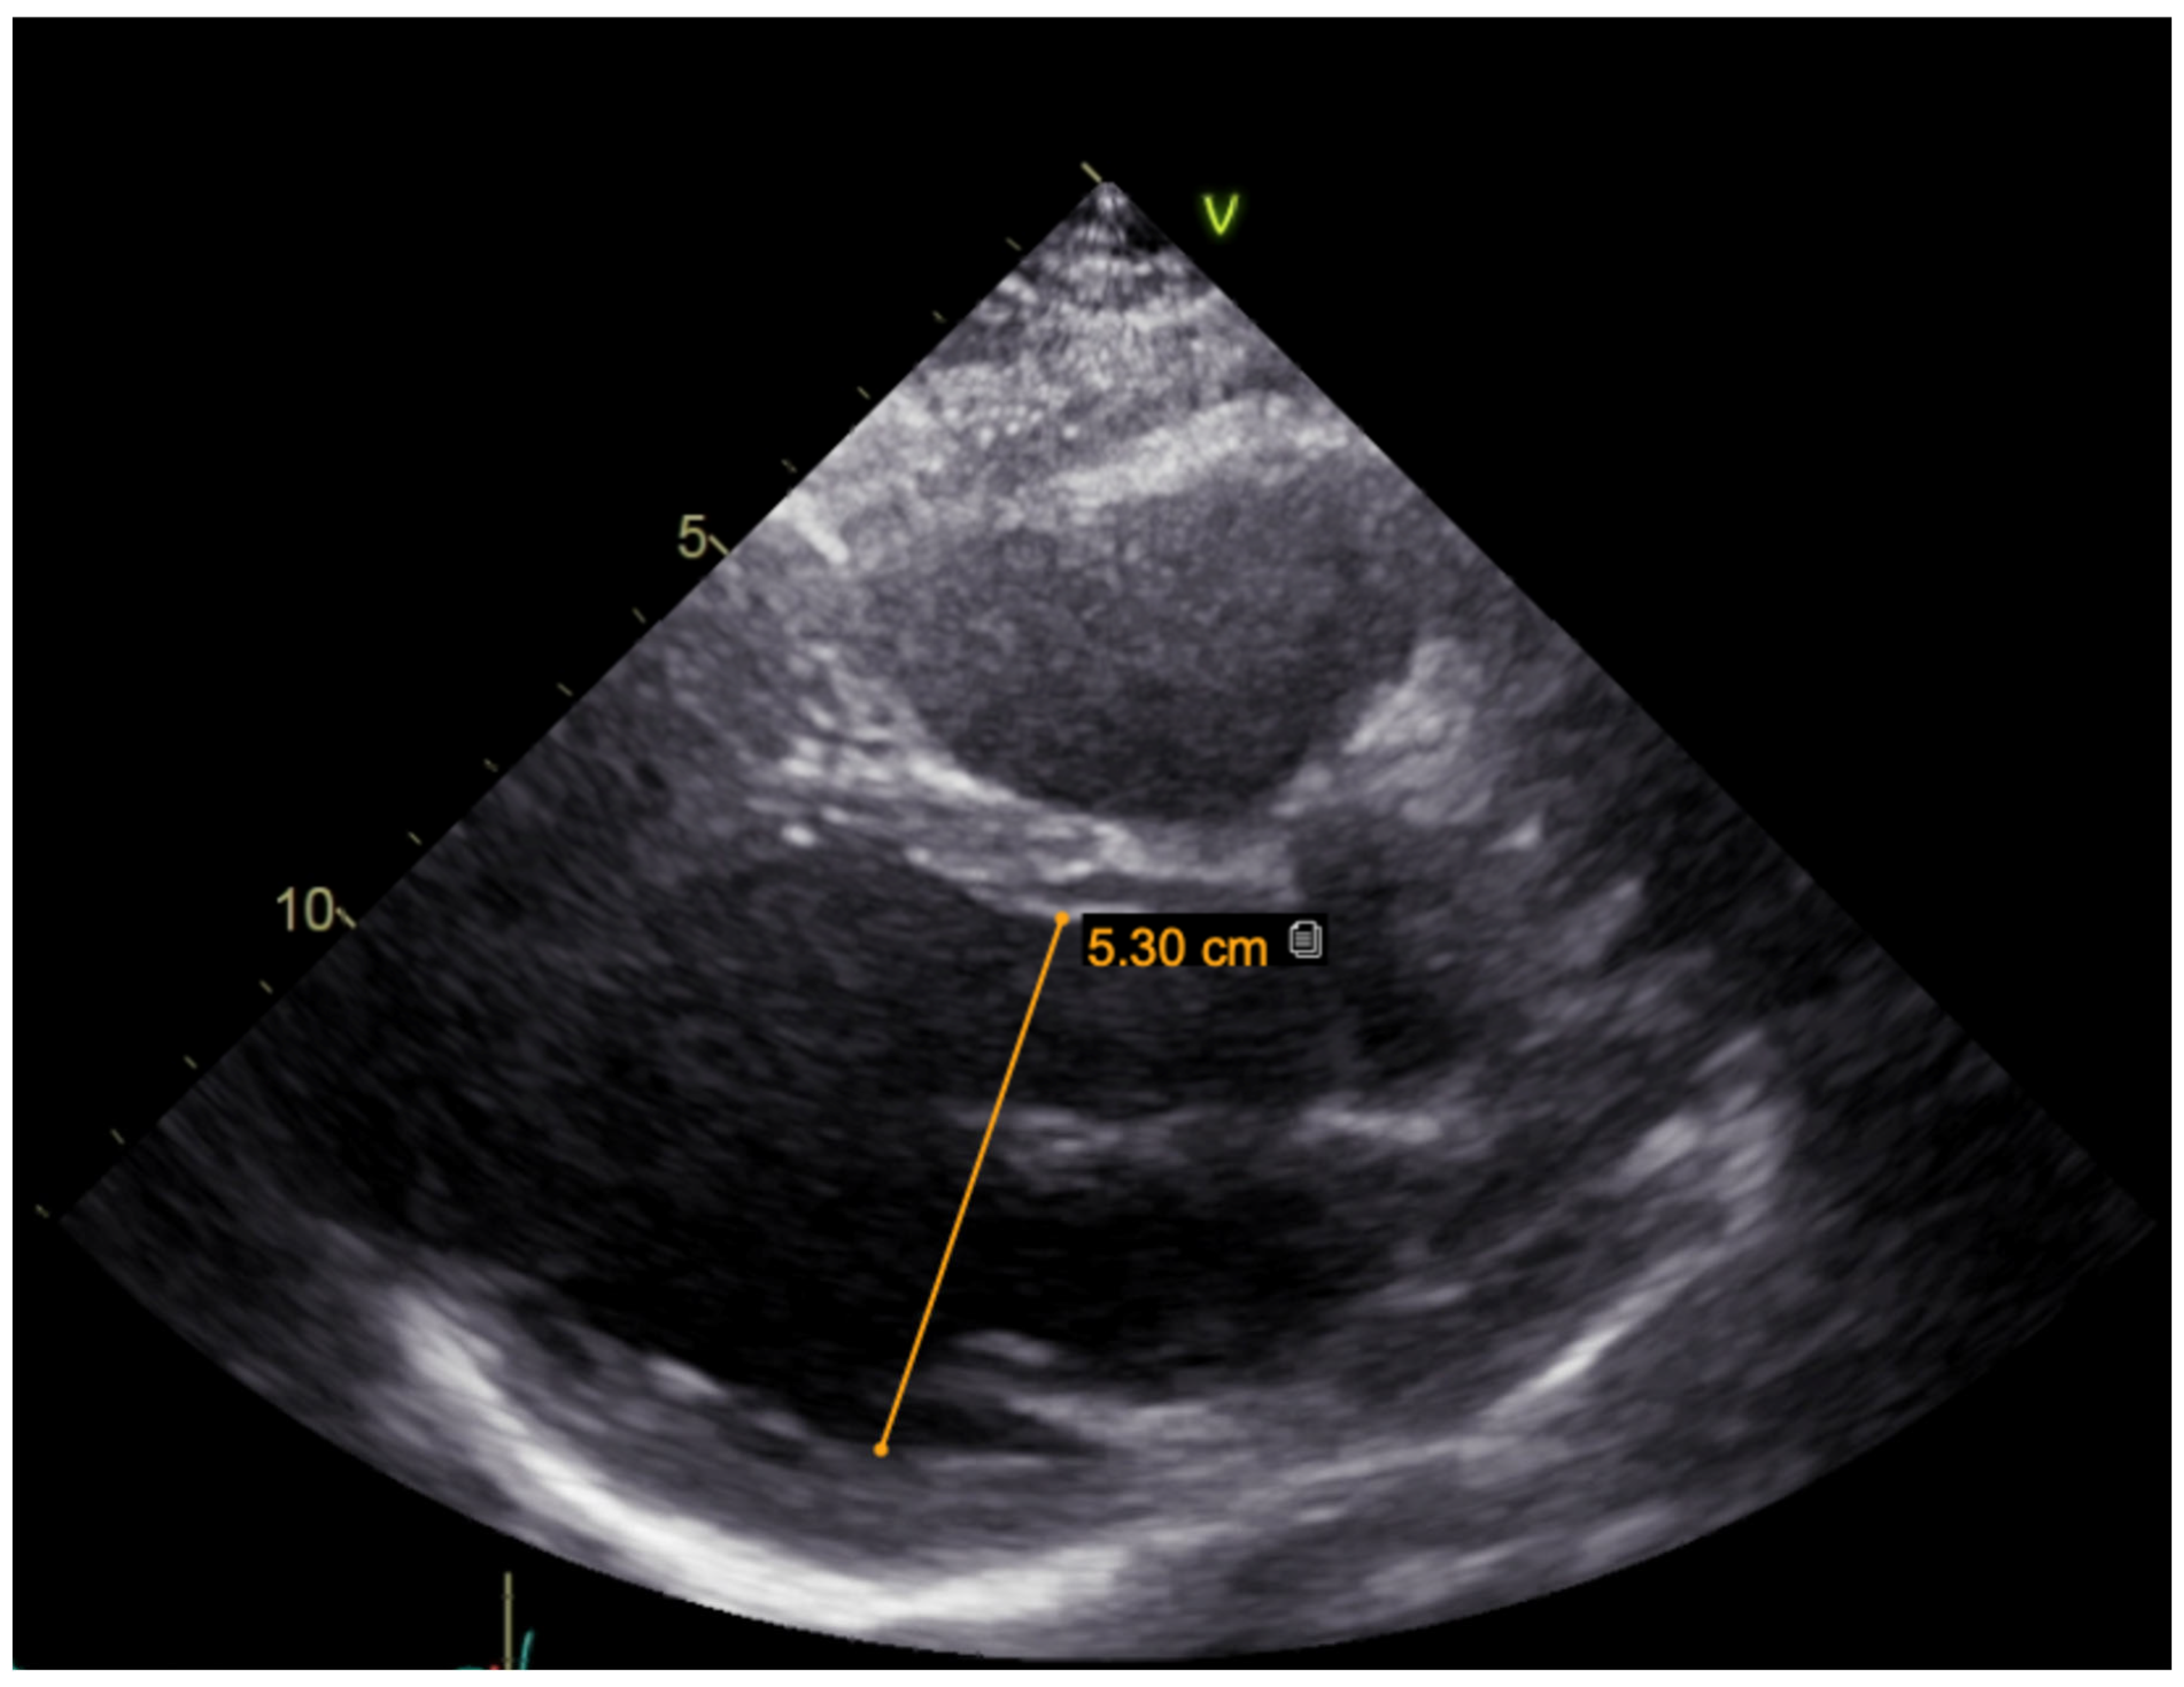

A hereditary disease was suspected, as the patient’s father died suddenly at the age of 40. Thus, targeted exonic sequencing of the SCN5A gene was performed. The pathogenic variant of the SCN5A gene (NM_198056.2) c.2440C > T (p.(Arg814Trp); rs199473161) was identified in a heterozygous state. The variant was advised to be evaluated according to clinical phenotype. It was decided to specify structural changes with repeated cardiac magnetic resonance imaging, although this scan was uninformative due to artefacts of ICD leads. Thus, TTE was repeated. No significant LV dilation (LVdd 54 mm) or systolic dysfunction (LV EF Simpson Biblane > 55%) were visible. The ergometry bicycle test demonstrated PVCs provoked by exercise, with most of them being monomorphic. A computerized tomography (CT) coronary angiogram ruled out coronary artery pathology, as the measured Agatston score was zero. During this time, the patient was on amiodarone and beta blockers. At the age of 31, the patient developed thyrotoxicosis and amiodarone had to be discontinued. Due to aggravated PVC symptoms, metoprolol was changed to 10 mg of bisoprolol per day. However, despite an optimized dose of beta blockers, the burden of PVCs increased, and approximately 66,491 (44%) PVCs were registered during 24 h Holter monitoring. TTE revealed a moderately dilated left ventricle (LVdd 57 mm, Figure 3) and impaired systolic function (LV EF 44%) in the context of ventricular bigeminy. A shared consultation with experts from the European Reference network of Rare Diseases was arranged, and a diagnosis of MEPPC syndrome was determined. Flecainide at a dose of 100 mg BID was added to bisoprolol at a dose of 10 mg. After several days, the dose of flecainide was increased to 300 mg a day, but no significant improvement in the patient’s status was observed. Thus, mexiletine was added, with the dose gradually titrated up to 150 mg three times a day. A substantial effect was seen in telemetry and registered in the ECG (Figure 4). All mentioned treatment adjustments were made during hospitalization in the arrhythmias department of Santaros Clinics, under telemetry surveillance, and with continuous monitoring of the patient’s clinical status. The patient was discharged with medical therapy of 7.5 mg of bisoprolol, 300 mg of flecainide, and 450 mg of mexiletine per day. During a follow-up visit after 1 month, a significant reduction in symptoms (fewer palpitations and better physical exercise tolerance), an improvement in LV function (LV EF by Simpson Biplane in repeated TTE was 53% and LVdd was 53 mm, Figure 5), and only 5819 (5%) PVCs under 24 h monitoring were observed. After 3 months, a further reduction to 858 (1%) PVCs under 24 h monitoring was registered and the patient had no complaints of palpitations. Dosages of antiarrhythmic drugs were reduced and as remission remained, discontinuation of mexiletine is under consideration.

Figure 3. TTE parasternal long-axis view before treatment (moderately dilated left ventricle, LVdd 57 mm).

Figure 5. TTE parasternal long-axis view after combination treatment (improvement in LV function, LVdd 53 mm).